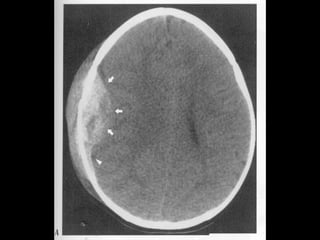

Plagă împuşcată. Fractură fronto-parietală stângă.Plagă împuşcată. Fractură fronto-parietală stângă.

Multiple fragmente de proiectilMultiple fragmente de proiectil